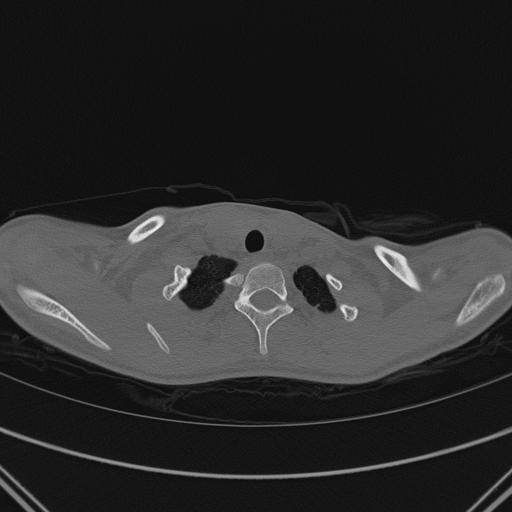

La TAC rileva, oltre a una modesta scoliosi sinistro-convessa del rachide cervico-dorsale, la fusione dell'estremit� anteriore della prima costa di destra con il terzo medio della sottostante costa e conferma l'assenza di anomalie morfostrutturali a livello claveare.

In conclusione tale malformazione congenita costituisce una massa retroclaveare tale da sublussare anteriormente l'articolazione sternoclaveare.

Figura 4. TAC della gabbia toracica superiore che evidenzia la fusione tra l'estremit� anteriore della prima costa di destra ed il terzo medio della sottostante costa